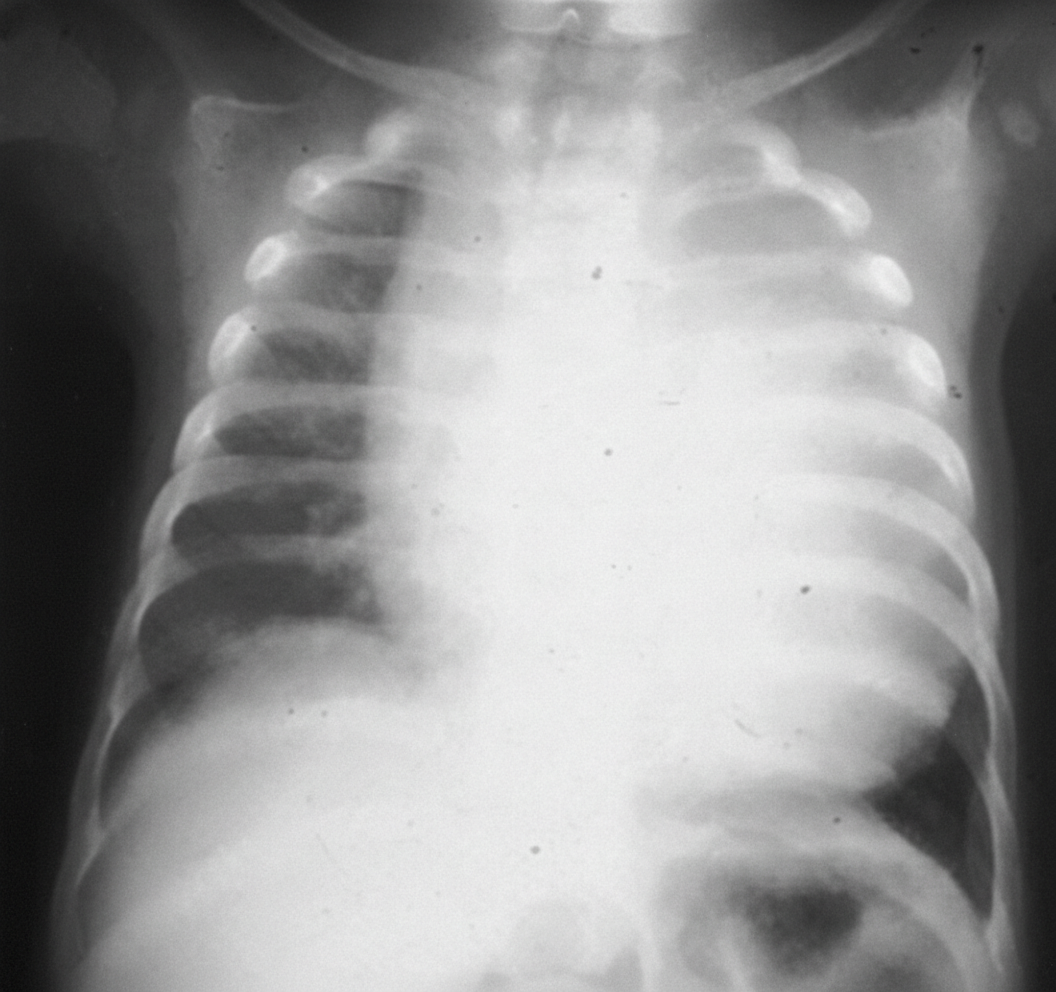

A patient presents with an X-ray showing cardiomegaly, along with symptoms of hypotonia, macroglossia, hepatomegaly, and floppy baby syndrome. The X ray of the infant is shown below. What is the most likely diagnosis?

Explanation: ***Pompe's disease*** - Pompe's disease (Type II glycogen storage disease) is characterized by a deficiency of **alpha-glucosidase**, leading to **glycogen accumulation** in lysosomes. - This accumulation results in **cardiomegaly**, **hypotonia** ("floppy baby"), **hepatomegaly**, and **macroglossia**, which perfectly match the clinical presentation. *Ebstein anomaly* - This is a congenital heart defect involving the **tricuspid valve**, leading to its displacement into the right ventricle. - While it causes cardiomegaly, it does not typically present with the systemic features like **hypotonia, macroglossia, or hepatomegaly** described. *Transposition of great arteries* - This is a complex congenital heart defect where the **aorta and pulmonary artery are switched**, resulting in two separate circulatory systems. - It causes severe cyanosis and cardiomegaly but does not explain the widespread glycogen storage symptoms such as **hypotonia** or **hepatomegaly**. *Von Gierke's disease* - **Von Gierke's disease** (Type I glycogen storage disease) is caused by a deficiency of **glucose-6-phosphatase**. - It primarily affects the **liver and kidneys**, causing severe hypoglycemia, hepatomegaly, and **nephromegaly**, but typically not significant cardiomegaly or profound hypotonia. *Congenital hypothyroidism* - Can present with **macroglossia, hypotonia, and hepatomegaly** similar to Pompe's disease. - However, the **massive cardiomegaly** seen on X-ray is not typical of hypothyroidism, and other features like prolonged jaundice, constipation, and umbilical hernia would be more prominent.